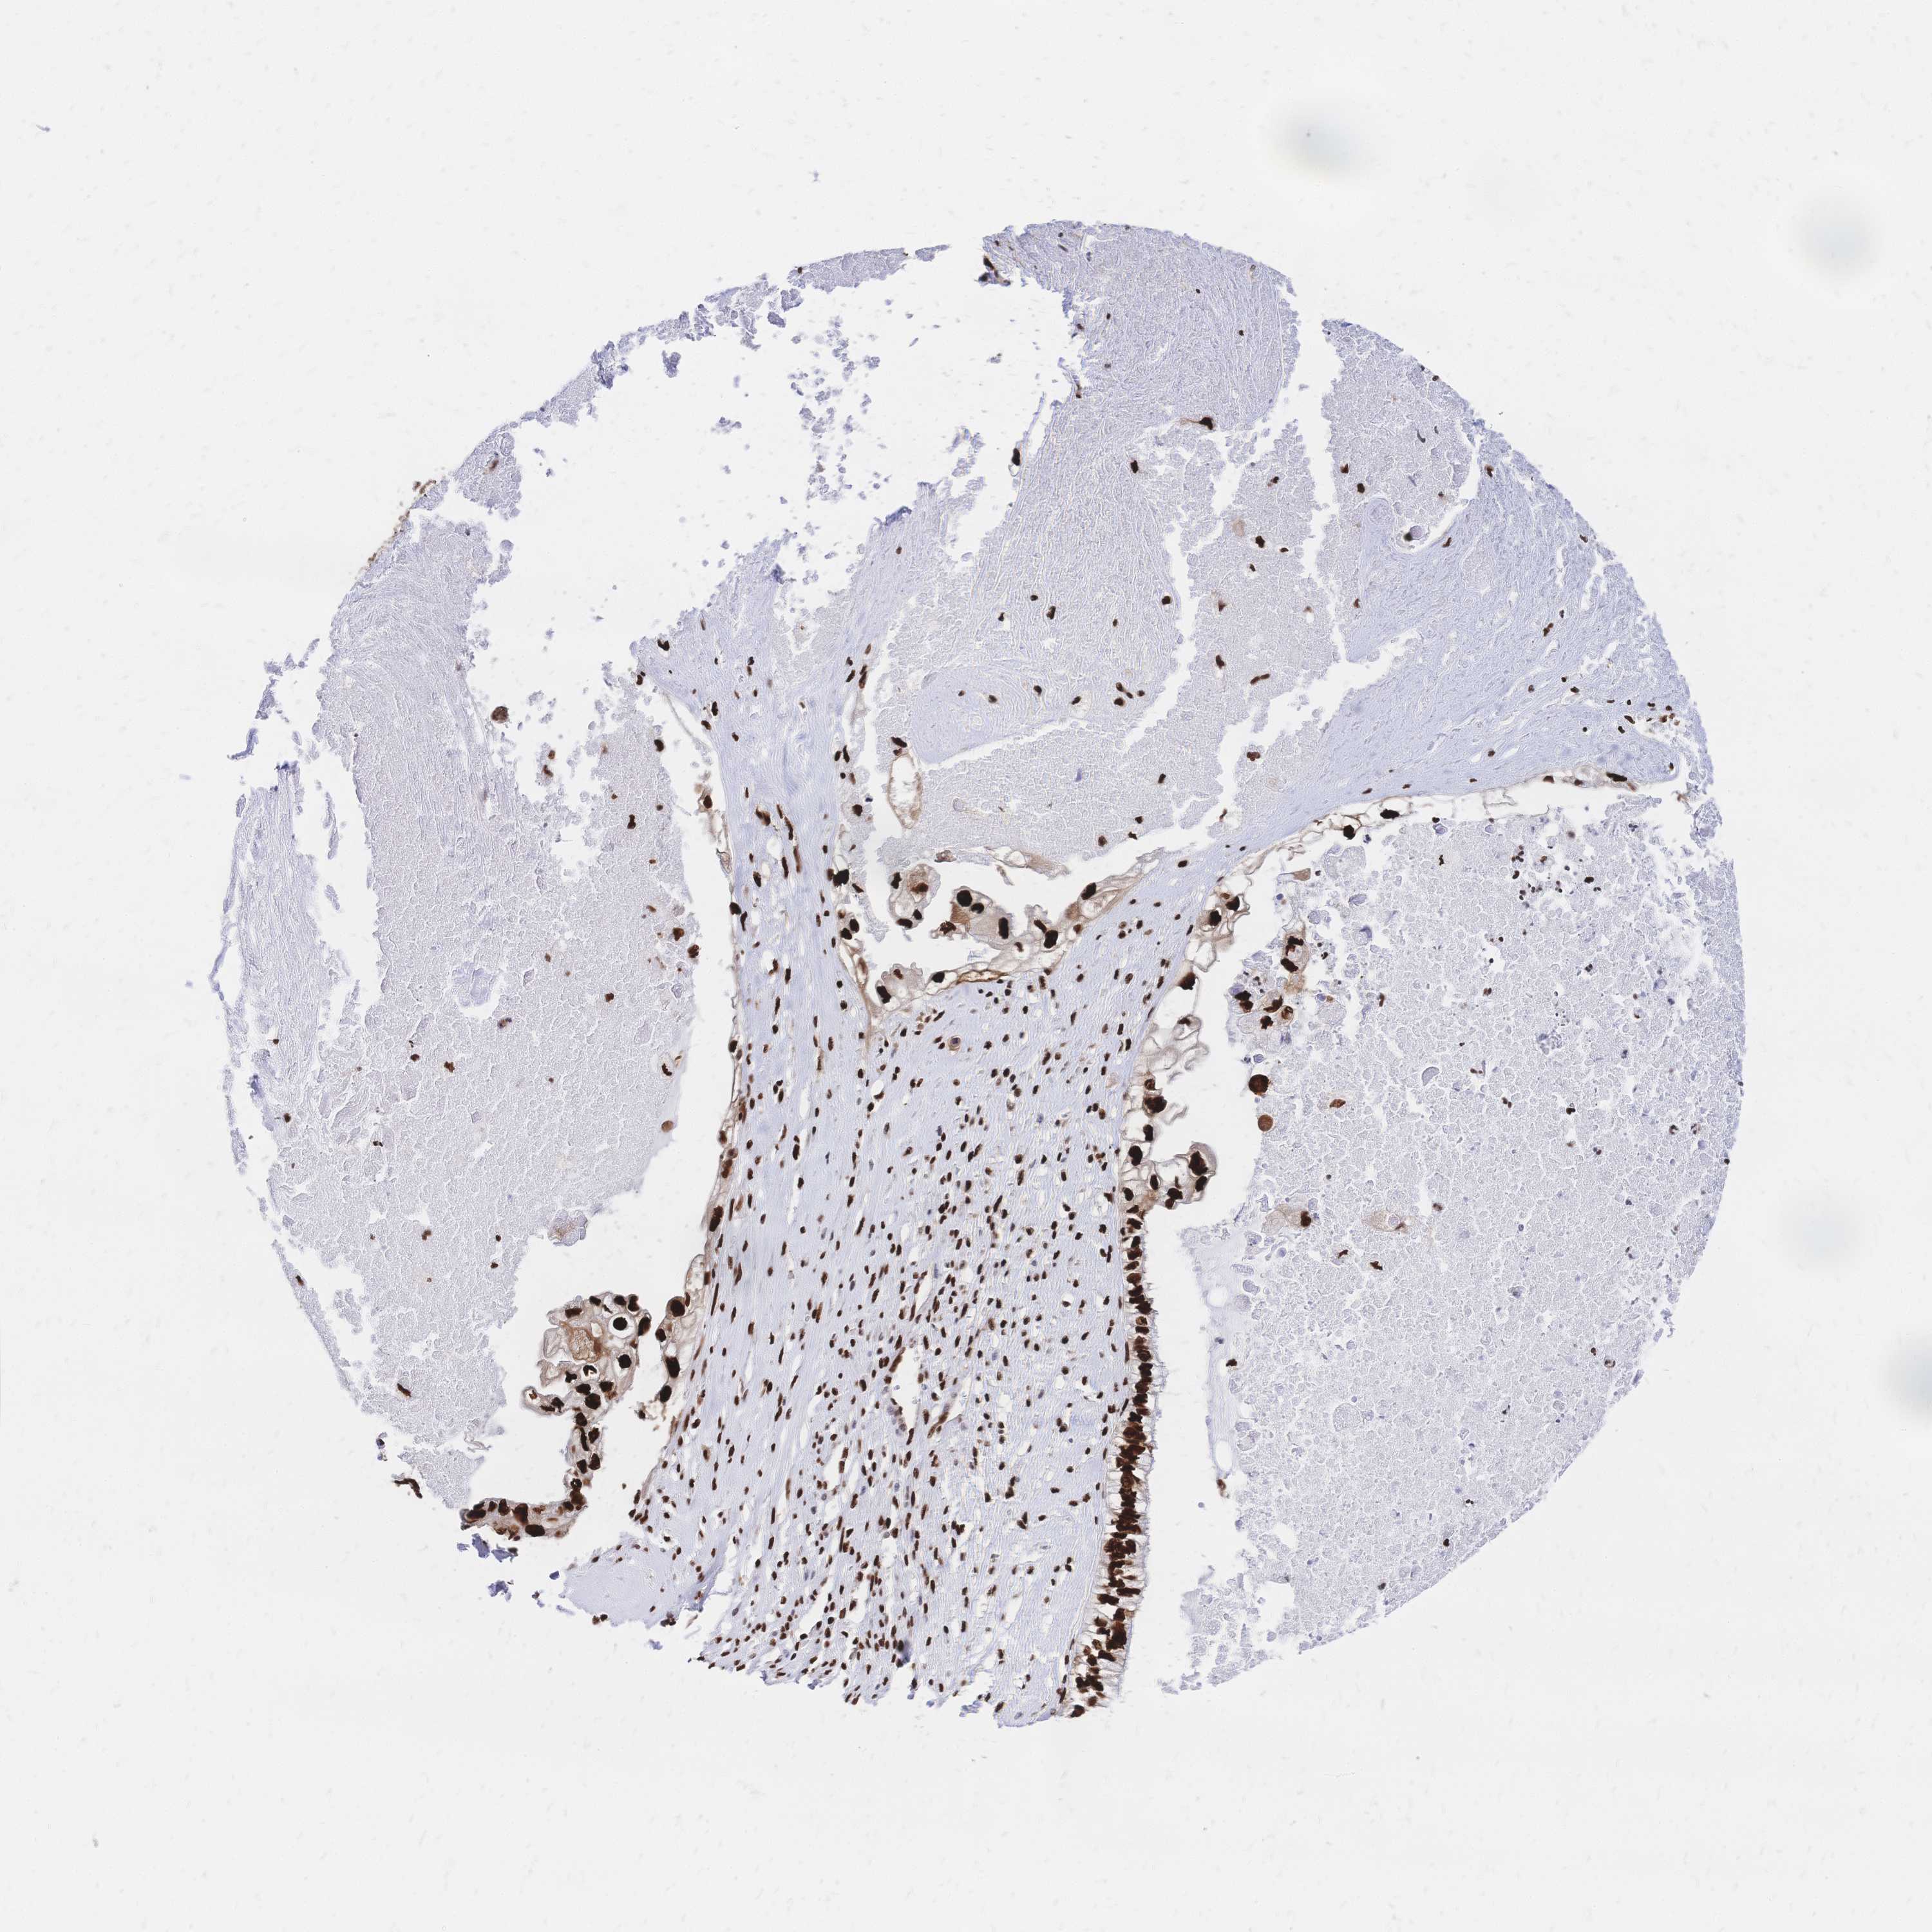

OVARIAN CANCER - Protein expressioni

A mouse-over function shows sample information and annotation data. Click on an image to view it in a full screen mode. Samples can be filtered based on level of antibody staining by selecting one or several of the following categories: high, medium, low and not detected. The assay and annotation is described here.

Note that samples used for immunohistochemistry by the Human Protein Atlas do not correspond to samples in the TCGA dataset.

Antibody stainingi

Antibody staining in the annotated cell types in the current human tissue is reported as not detected, low, medium, or high, based on conventional immunohistochemistry profiling in selected tissues. This score is based on the combination of the staining intensity and fraction of stained cells.

Each image is clickable and will lead to virtual microscopy that enables deeper exploration of all samples and also displays staining intensity scores, fraction scores and subcellular localization as well as patient and tissue information for each sample.

Antibody HPA048728

Antibody HPA053422

Antibody CAB026035

Cystadenocarcinoma, serous, NOS

Cystadenocarcinoma, mucinous, NOS

Adenocarcinoma, NOS

Carcinoma, endometroid

Carcinoma, NOS